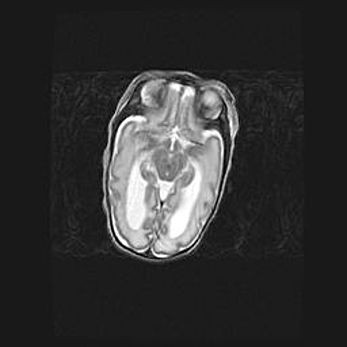

Неполная лизэнцефалия (пахигирия). Открытая гидроцефалия.

Возраст: 17 дней

Вес: 3110 г

Пол: мужской

Окружность головы: 33,5 см

Срок гестации: 35-36 недель

Лизэнцефалия—недоразвитие корковой пластинки и мозговых извилин в результате нарушения миграции нейронов коры. Поверхность мозговых полушарий гладкая. Микроскопически выявляется отсутствие нормальных слоев коры и скопление групп нейронов в подкорковом белом веществе.

Пахигирия—уменьшение числа вторичных извилин. В пораженном полушарии нервные клетки образуют толстый недифференцированный слой с неправильно расположенными нервными волокнами и группами гетеротопных клеток. Нервные клетки незрелые. Белое вещество истончено. При этом нередко аномально развит корково-спинномозговой путь.